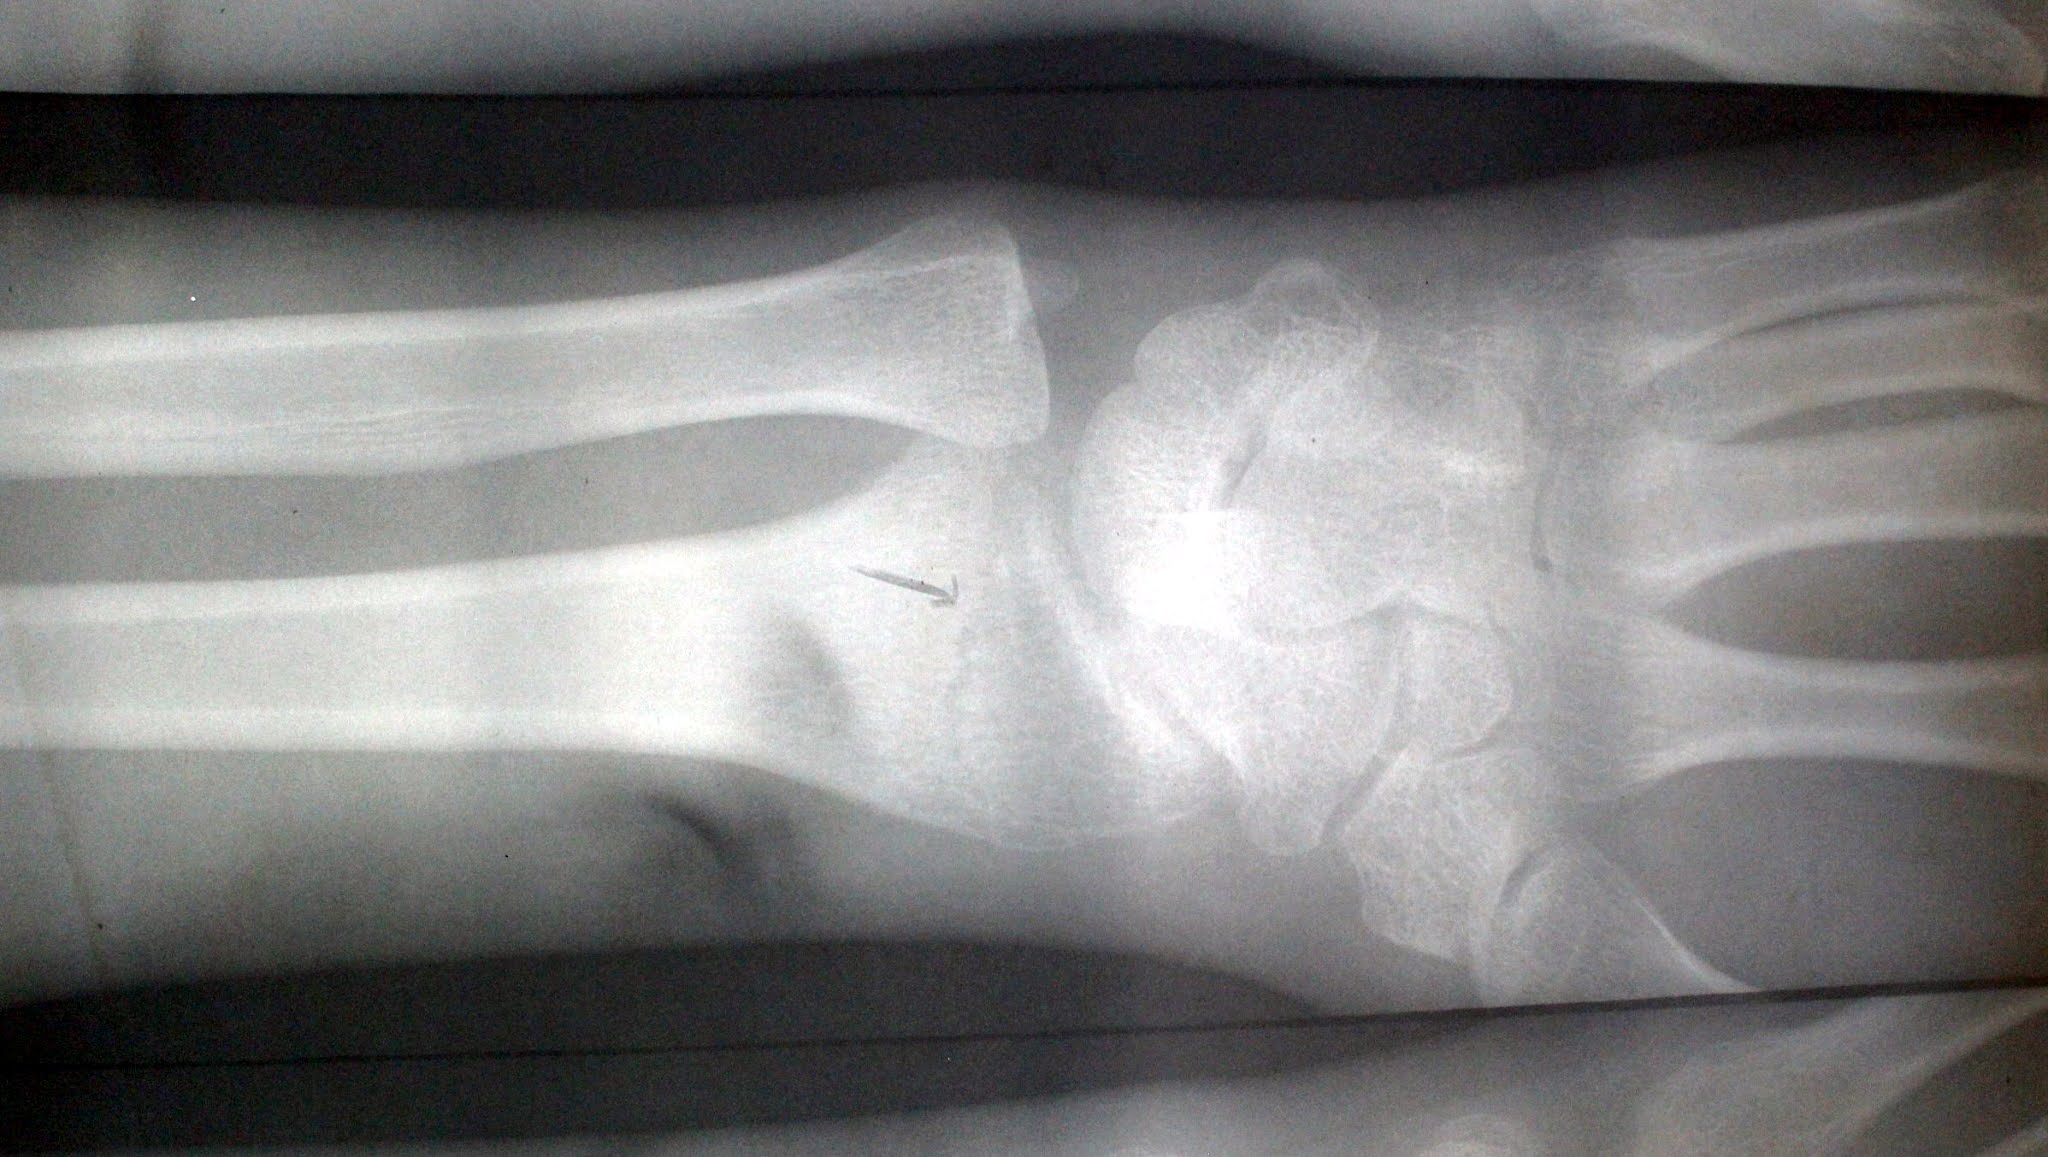

ヨセミテ公園の病院で撮影した

レントゲン写真

(撮影日:1968-6-2)

以下の画像は、サニーヴェイルの医者がギプスをはずした直後に撮影したものであることが分かった(私はヨセミテの医者が撮影したものと誤解していた)。

ギプスをはずした直後の画像

3つの画像が1枚のフィルム

に圧縮されている

(撮影日:1968-7-9)

前図の真ん中の画像を拡大したもの

矢印が、骨折線を指し示している

サニーヴェイルの医者が、すべてのX線写真のネガ(全部で9枚程あったのだと思われる)を取り寄せてそのコピーから圧縮して4枚のネガフィルムを作ってくれたらしい。各々のフィルムには撮影日まではっきりと表示されていた。しかももう一人別の医者が関係していて、多分X線写真を読み取って診断できる専門の医師なのであろう。詳しい診断書まで添えられていたのである。

専門医による診断書(S.M. Glasser, M.D. July 9, 1968)の内容

RIGHT WRIST:

There is an oblique fracture of the distal end of the radial shaft. The more medial distal projection of the fracture line extends to the articular surface of the radius. The fragments are in excellent apposition and alignment. The fracture line, however, is still clearly discernible with very minimal evidence of callus formation. There is no change in the good position of the fragments contrasted with a film taken at the Lewis Memorial Hospital, dated 6-2-68.

IMPRESSION:

Well healing fracture, distal end of radial shaft, with good position of fragments and minimal callus formation.

日本語訳(医学の専門用語に疎いので訳はいい加減です)

右手首:

橈(とう)骨の遠位端に斜めの骨折がある。骨折線のより内側の遠位突起は、橈骨の関節面まで伸びている。断片は良好な位置にある。しかし骨折線は依然としてはっきりと識別可能であり、カルス形成の可能性はごくわずかだが残っている。1968-6-2 付けのルイス記念病院で撮影されたフィルムとは対照的に、断片の良好な位置に変化はない。

感想:

骨折の治癒が良好で、橈骨の遠位端で断片の位置は良好であり、カルス形成が最小限に抑えられている。